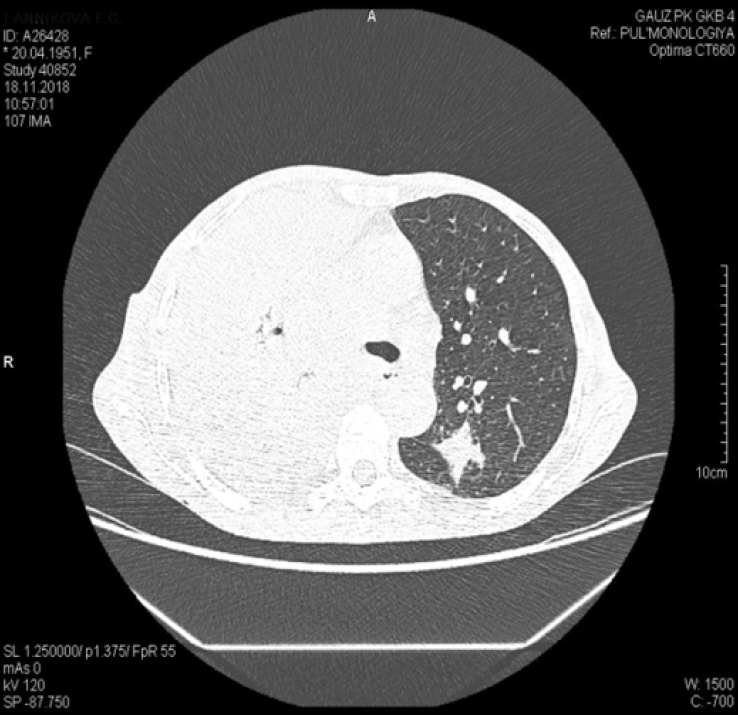

Рентгенография органов грудной клетки (ОГК) от 10.11.2018: легкие эмфизематозны справа в среднем поле, в проекции S6 снижена прозрачность за счет инфильтрации с полостями деструкции и с вовлечением прилежащей плевры, в плевральной полости жидкость с косым уровнем по переднему отрезку 5-го ребра. Левое легкое без инфильтративных изменений, парамедиастинально на уровне 4-го межреберья визуализируется плотная очаговая тень 10×15 мм с довольно четким контуром. Легочный рисунок деформирован за счет явлений пневмосклероза (рис. 2).

Рис. 2. Рентгенограмма органов грудной клетки от 10.11.2018 (позитив)

Рентгенография ОГК от 14.11.2018 – отмечается отрицательная динамика: справа нарастает субтотальное затемнение за счет ателектаза средней и нижней долей, а также жидкости с паракостальным распространением и плевральных наслоений. Слева легкое без инфильтративных изменений. В проекции «головки» левого корня плотная очаговая тень 10×15 мм с довольно четким контуром. Легочный рисунок деформирован за счет явлений пневмосклероза. Средостение смещено вправо (рис. 3).

Рис. 3. Рентгенограмма органов грудной клетки от 14.11.2018